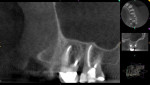

The radiographic examination with digital 2D radiographs revealed a diffuse radiolucency at the apices and a widened lamina dura for tooth No. 15 (Figure 5). The patient underwent a CBCT study (Kodak 9000) for further evaluation of the area. The CBCT scan revealed two dome-shaped radiopacities of soft-tissue density superior to teeth Nos. 14 and 15 and a large 8 mm x 8 mm periapical lesion associated with the palatal root of No. 15 with penetration through the cortical bone into the sinus. Tooth No. 14 revealed a periapical radiolucency at the MB root due to an unobturated mesiolingual (ML) canal (Figure 6).